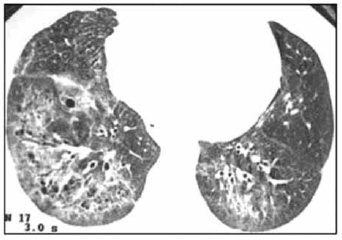

Mulher, 46 anos, procura atendimento médico com queixa de sensação de fraqueza e adinamia. Observou que, principalmente em dias mais frios, apresenta palidez e cianose em extremidades. Além disso, já procurou dermatologista por queda de cabelo, além de espessamento e endurecimento da pele. Houve surgimento de diversas lesões de pele com características de teleangiectasias e, recentemente, passou a cursar com disfagia a alimentos sólidos e dispneia aos pequenos esforços. O ecocardiograma transtorácico revelou PSAP de 70 mmHg, e um corte da tomografia de tórax realizada está ilustrado a seguir.

Considerando a principal hipótese diagnóstica, sabe-se que o autoanticorpo que se correlaciona aos achados e a mau prognóstico é o